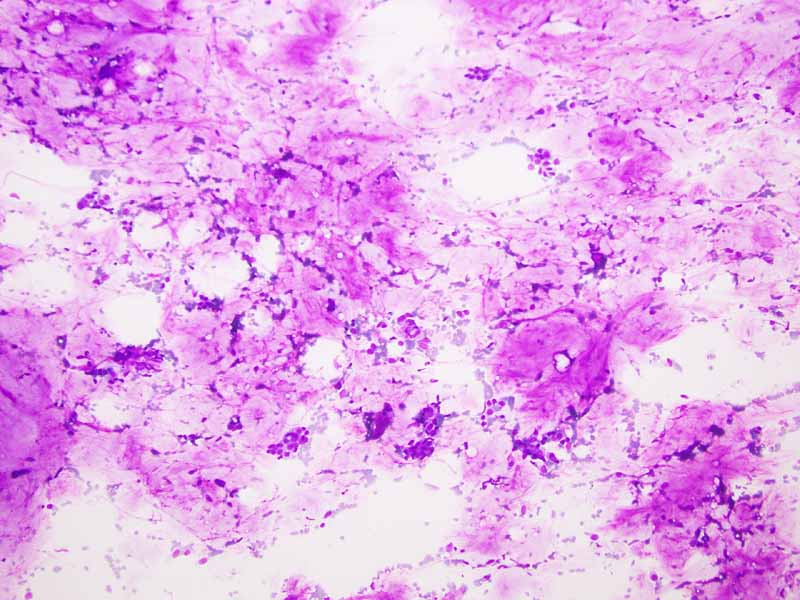

Cytology of the Case: The background is dominated by a substantial amount of mucoid material (Panel A) and admixed with these materials are small clusters of neoplastic cells. Some delicate blood vessels are also present (Panel B). A small number of tumor cells are adhered to these blood vessels but there is a lack of genuine papillary arrangement. The cells are epithelioid and contains a moderate amount of cytoplasm (Panel B, C, D, E, and F) that are finely vacuolated (Panel D and F) in some of them. The neoplastic cells are rather adhesive to each other. The nuclei are hyperchromatic and without pseudonuclear inclusion in most of them. There is no prominent nucleoli A minute amount of tissue is present in the cell block (Panel G). There is definitive gland formation. Some spindle neoplastic cells (S in Panel G) are also present next to the glandular structure. The nuclear features of these cells are identical to that of the glandular cells.

Histology of the Case: The lesion is an encapsulated neoplasm a glandular component and a myxoid component (Panel I and J). The two comonents are well demarcated without transition from one into another. Although the myxoid component (Panel K and L) is not present in the cell block of the FNA, the myxoid substance of the FNA comes from this myxoid component. The glandular component (Panel M, N, O, P) is composed of well formed glands with PAS positive mucoid content in the lumen (Panel Q). In between the well formed glands are spindle cells with nuclear features identical to that of the glands (S in Panel N). This component is present in the cell block of the FNA and is the major clue for the diagnosis.

Highlight of this case: This case has a myxoid predominant and epithelial predominant component that are distnctly separated. Small FNA from these components can lead to different interpretation that span from a myxomatous soft tissue tumor to metastatic carcinoma. Although the histopathology and immunohistochemical profile are classic for a biphasic synovial sarcoma, it lacks the classic translocation of SS18 which is seen in most synovial sarcomas.